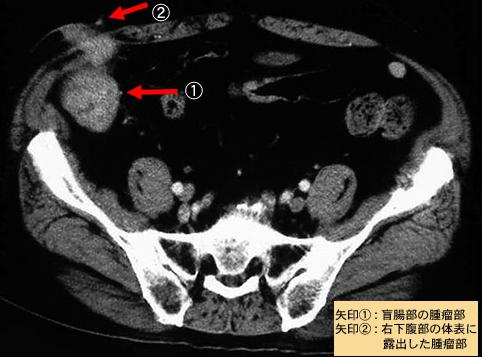

질환(병리주체)의 분류 악성 상피성종양/선암

부위(장기별) 대장/맹장

검사방법 CT

종양의 육안분류 1형(종괴형)/

종양의 최대경(밀리미터) 40이상

종양의 심달도 s(a)